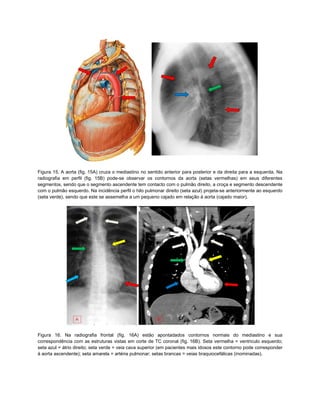

Figura 15. A aorta (fig. 15A) cruza o mediastino no sentido anterior para posterior e da direita para a esquerda. Na

radiografia em perfil (fig. 15B) pode-se observar os contornos da aorta (setas vermelhas) em seus diferentes

segmentos, sendo que o segmento ascendente tem contacto com o pulmão direito, a croça e segmento descendente

com o pulmão esquerdo. Na incidência perfil o hilo pulmonar direito (seta azul) projeta-se anteriormente ao esquerdo

(seta verde), sendo que este se assemelha a um pequeno cajado em relação à aorta (cajado maior).

Figura 16. Na radiografia frontal (fig. 16A) estão apontadados contornos normais do mediastino e sua

correspondência com as estruturas vistas em corte de TC coronal (fig. 16B). Seta vermelha = ventriculo esquerdo;

seta azul = átrio direito; seta verde = veia cava superior (em pacientes mais idosos este contorno pode corresponder

à aorta ascendente); seta amarela = artéria pulmonar; setas brancas = veias braquiocefálicas (inominadas).